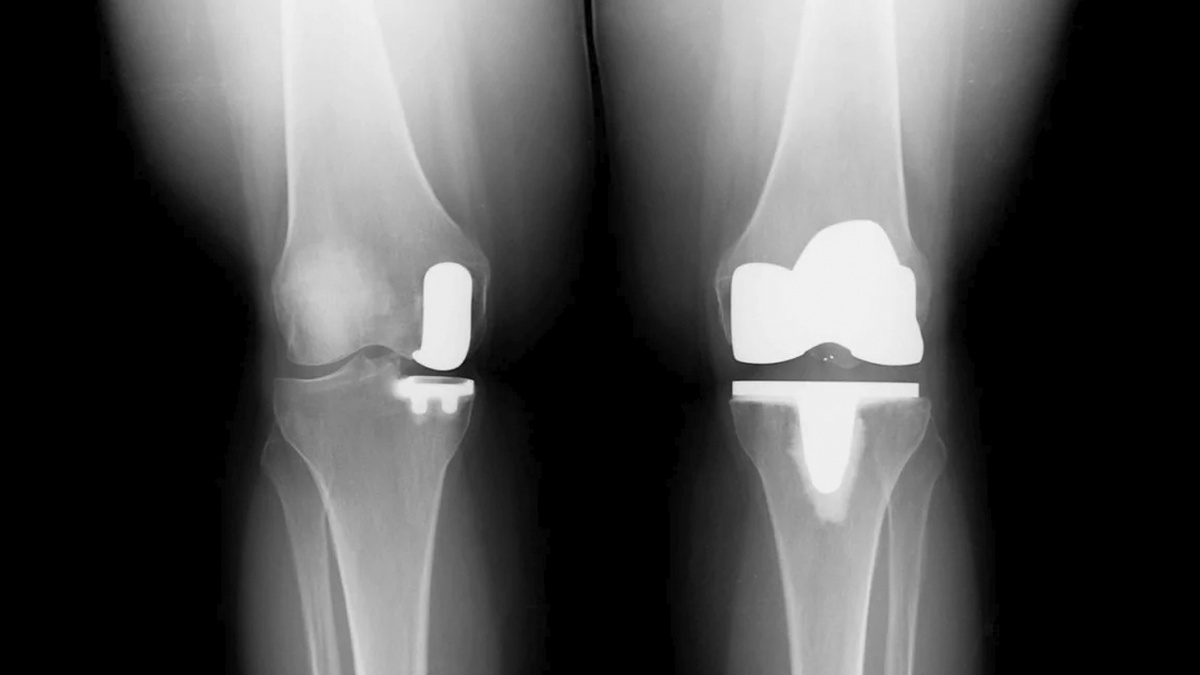

Только проанализировав снимки врач сможет точно оценить, подходит ли пациенту одномыщелковое эндопротезирование. Кстати, мои подписчики могут прислать снимок для консультации, все контакты по ссылке: http

Только проанализировав снимки врач сможет точно оценить, подходит ли пациенту одномыщелковое эндопротезирование. Кстати, мои подписчики могут прислать снимок для консультации, все контакты по ссылке:

Это операция, при которой заменяется только один из мыщелков (внутренний или наружный) коленного сустава, а здоровые части остаются нетронутыми.